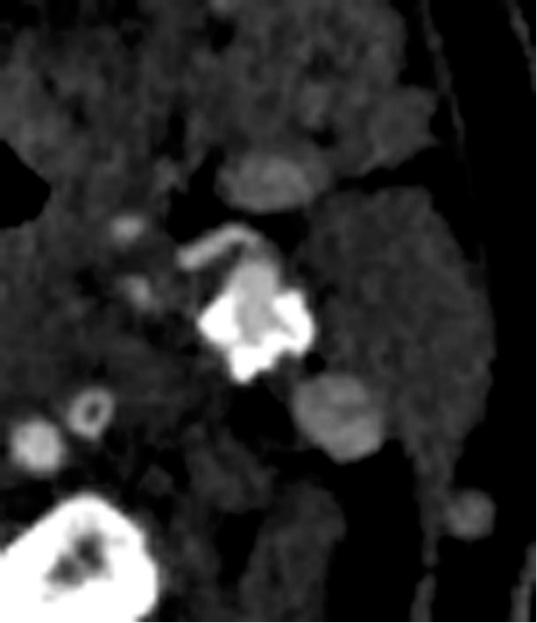

Заметим, что у всех пациентов, интима которых разрывалась при давлении до 200 мм рт. ст., имелся жидкостной компонент бляшки, а у 6 пациентов, критическое давление на бляшку у которых было 150 мм рт. ст., отмечалась еще и истонченная «покрышка» бляшки (рис. 5).

Рис. 5. Компьютерная томограмма пациента с нестабильной атеросклеротической бляшкой. Определяется единая большая полость внутри бляшки с жидкостным компонентом (черная стрелка) и истонченная покрышка (белая стрелка)

Fig. 5. Сomputed thomography of a patient with unstable atherosclerotic plaque. A single large cavity inside the plaque with a liquid component (black arrow) and a thinned «cover» (white arrow)